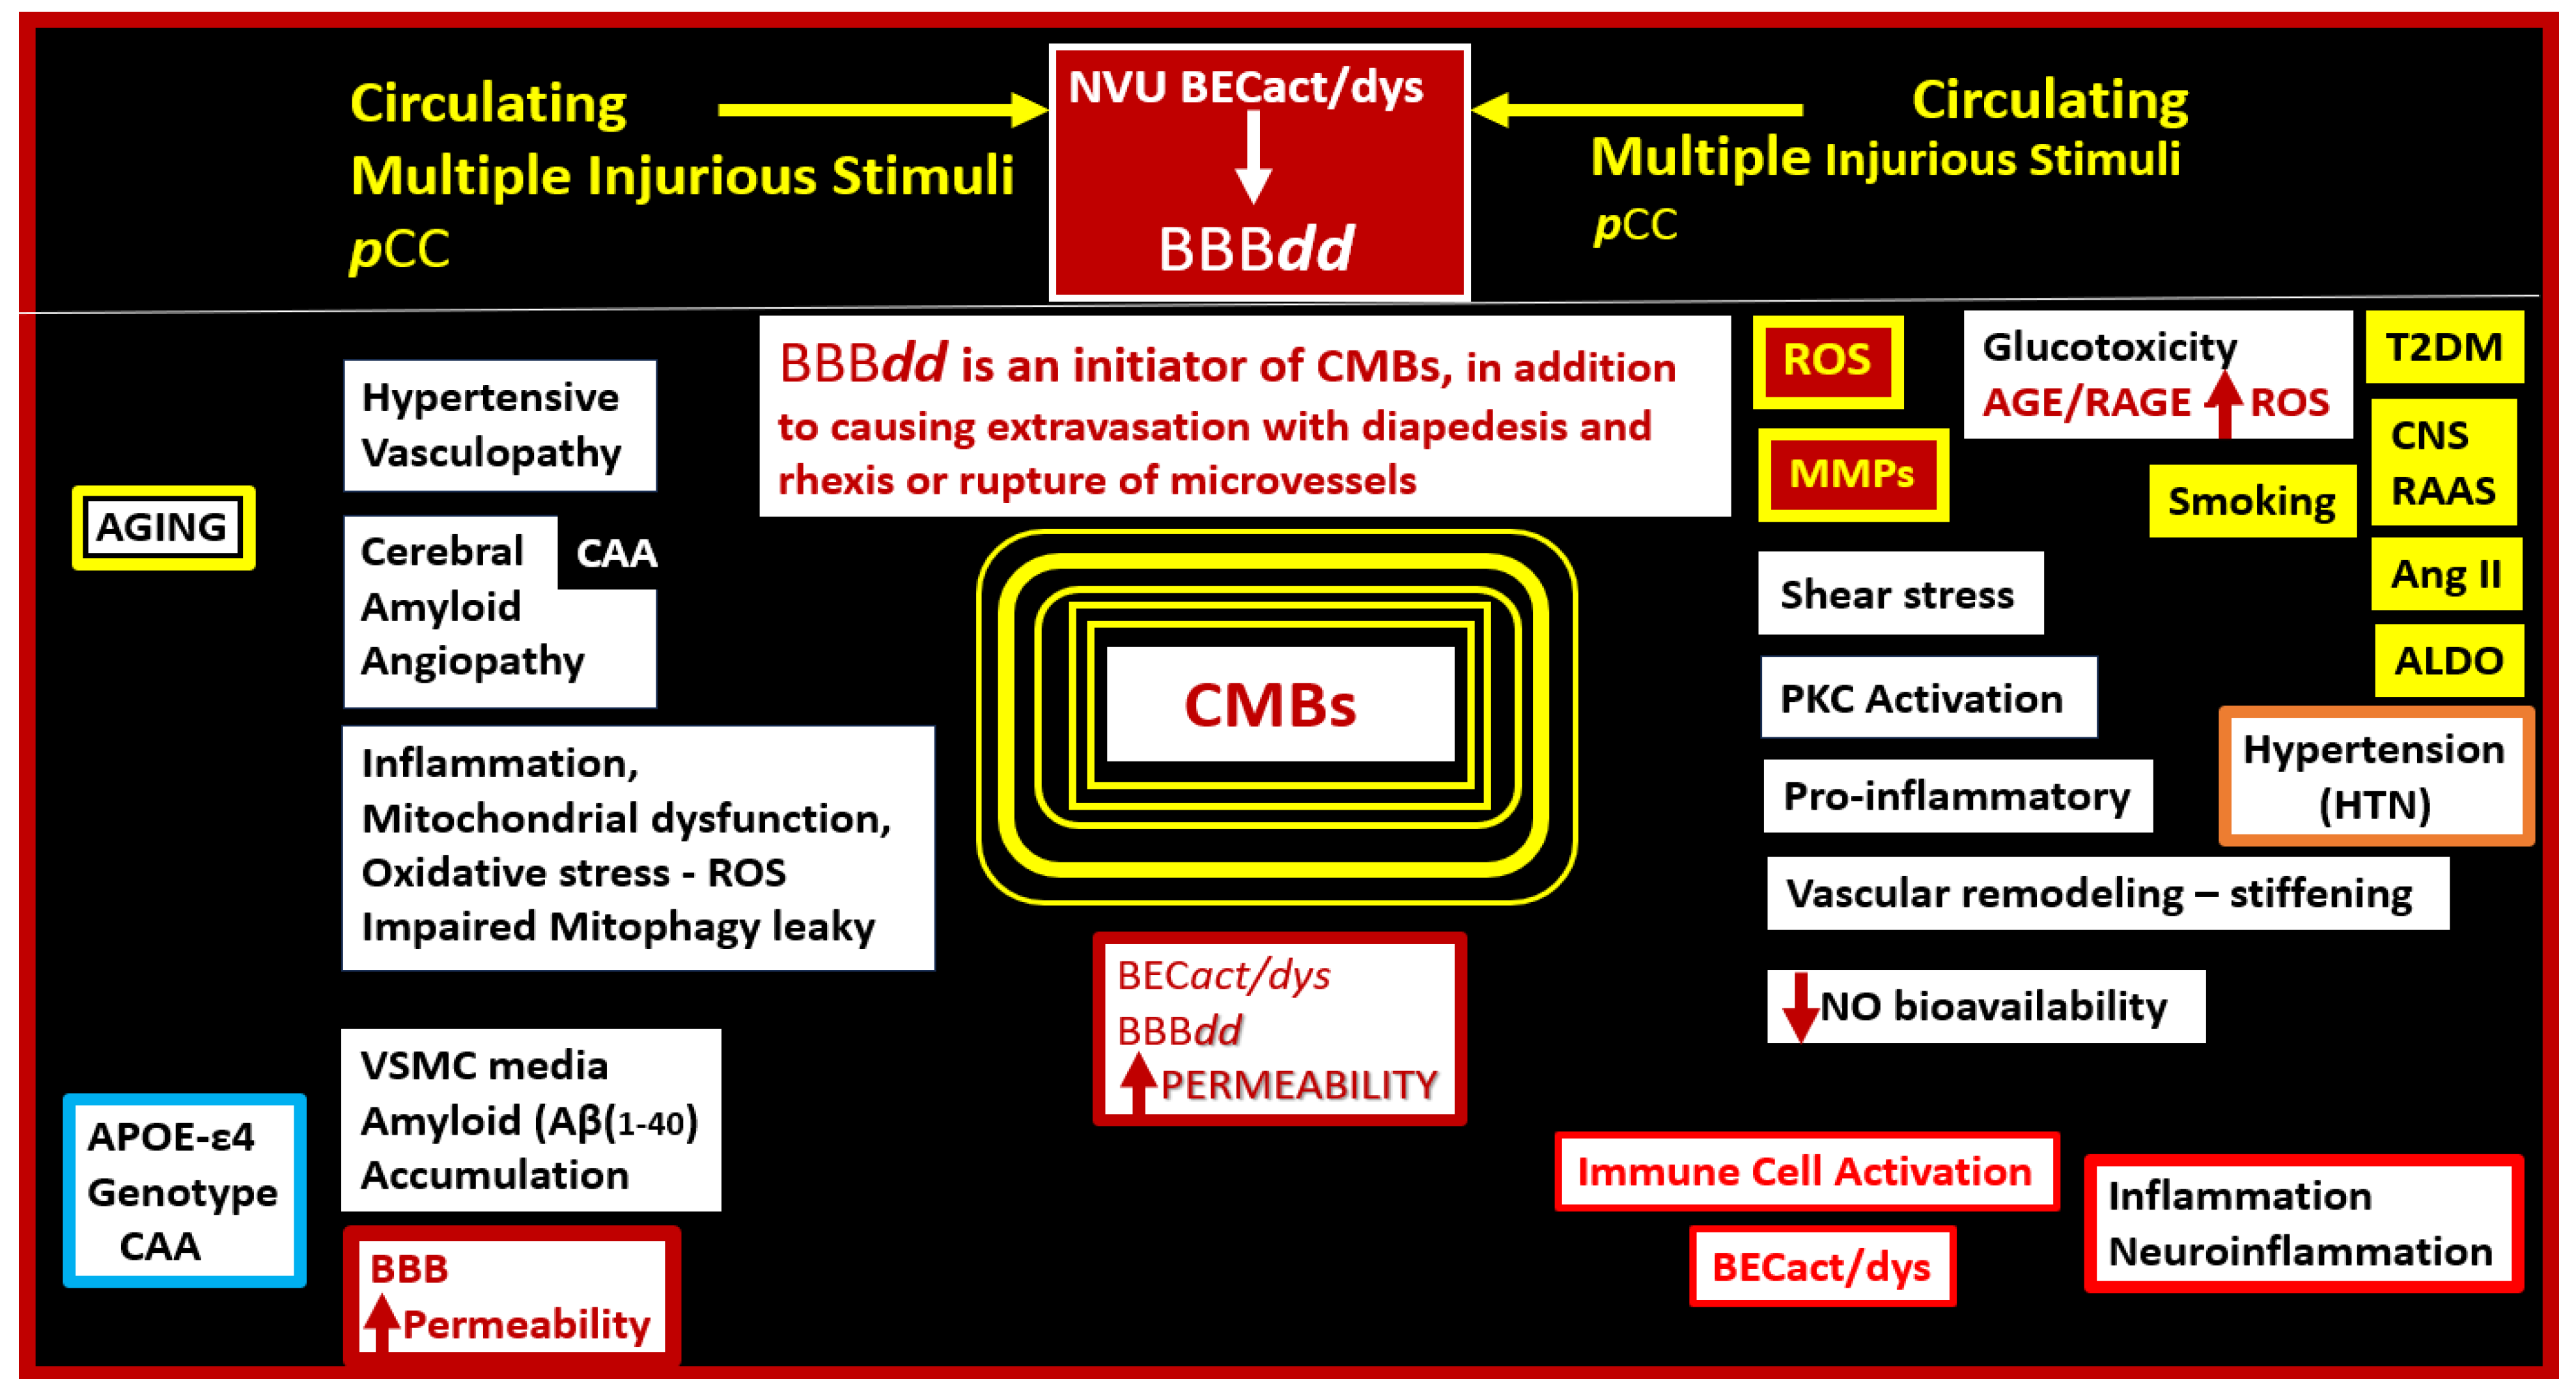

2. A Possible Sequence of Events in the Development of Cerebral Microvessel Bleeds (CMBs)

2.1. Brain Endothelial Cell Activation and Dysfunction (BECact/dys)

2.2. Blood–Brain Barrier Dysfunction and/or Disruption (BBBdd) with Increased Permeability

2.3. Hypertensive (HTN) Vasculopathy

2.4. Cerebral Amyloid Angiopathy (CAA)

Oxidative—Redox Stress: Implications in the Development of CAA, LOAD, SVD, and CMBs